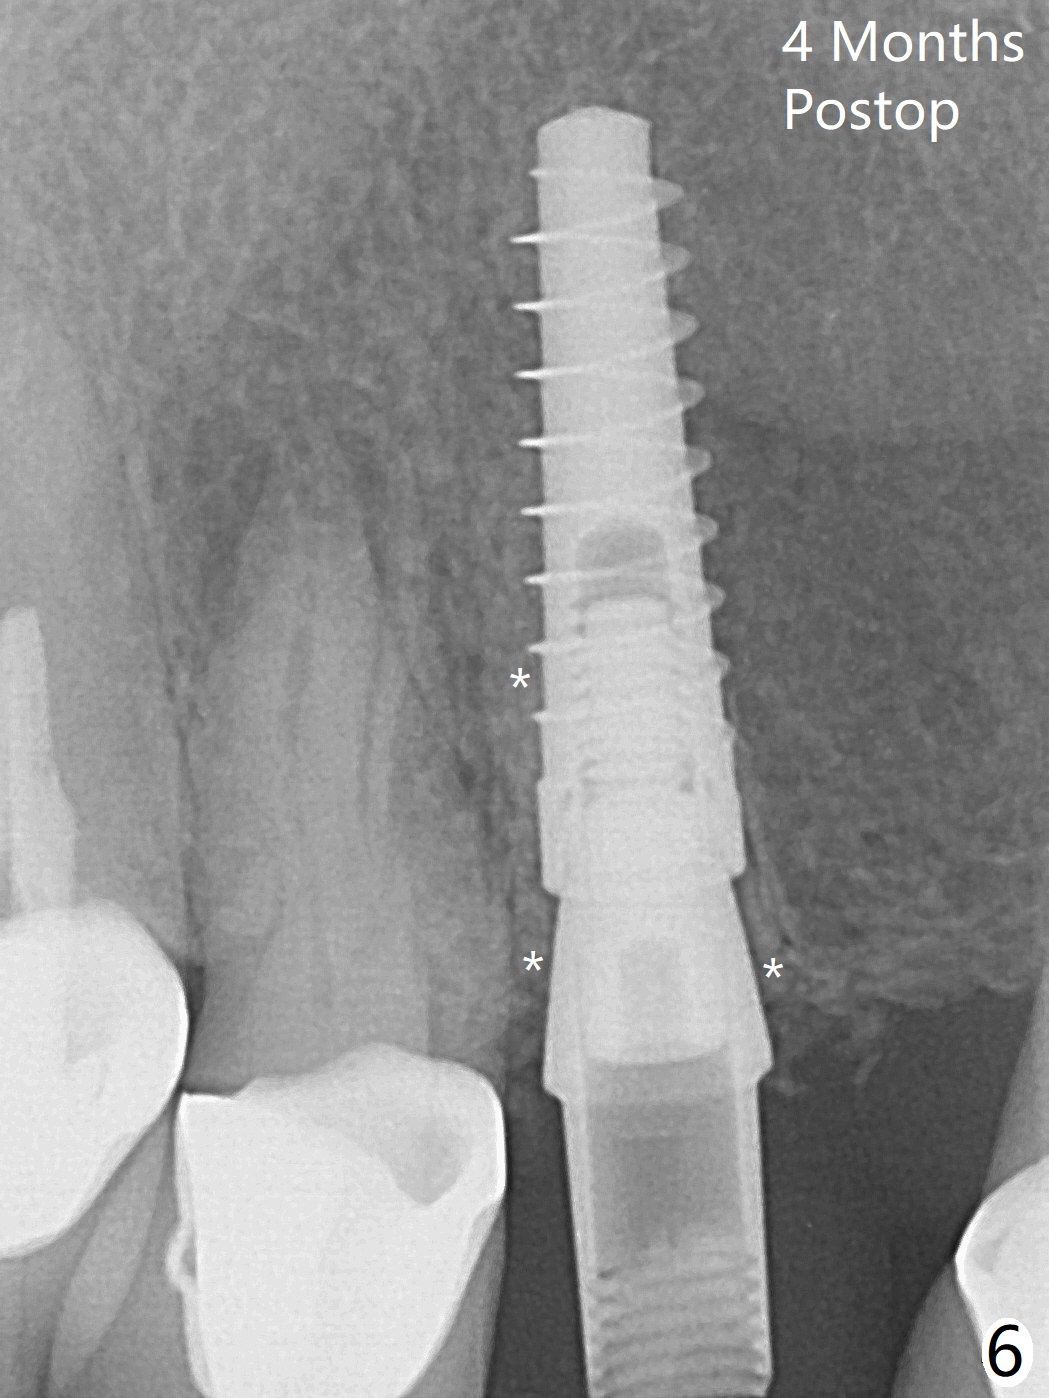

To reduce the large black triangle between the lateral incisor/canine and central incisor (Fig.1 *), osteotomy is not established mesial enough initially (Fig.2). Since the bone density is not high, trajectory change is not attempted. The ridge is wider within the socket. A relatively large 2-piece implant (3.5x13 mm) is placed (Fig.3), but a 4x5.7(2) mm abutment is incompletely seated (<). Use of 4.6 and 5.6 mm bone profile drills does not appear to solve the problem. The implant is backed up to the supra-gingival level so that it seems easier physically to insert the same abutment into the implant. Then both of them are torqued into the place together (Fig.4). An immediate provisional is fabricated to close the gingival embrasure as much as possible (Fig.5). Consider reducing the provisional margin (arrow) as early as possible postop. In fact the patient agrees to have a new crown made for #8 to further close the embrasure. The bone graft remains in place 4 months postop (Fig.6). The gingiva is healthy around the provisional 4.5 months postop (Fig.7). The gingival embrasure with a permanent restoration is smaller than that before treatment (Fig.8). Return to No Deviation Prevent Screw Loosening Prosthetic Planning Kit Webinars Xin Wei, DDS, PhD, MS 1st edition 02/11/2020, last revision 07/09/2020